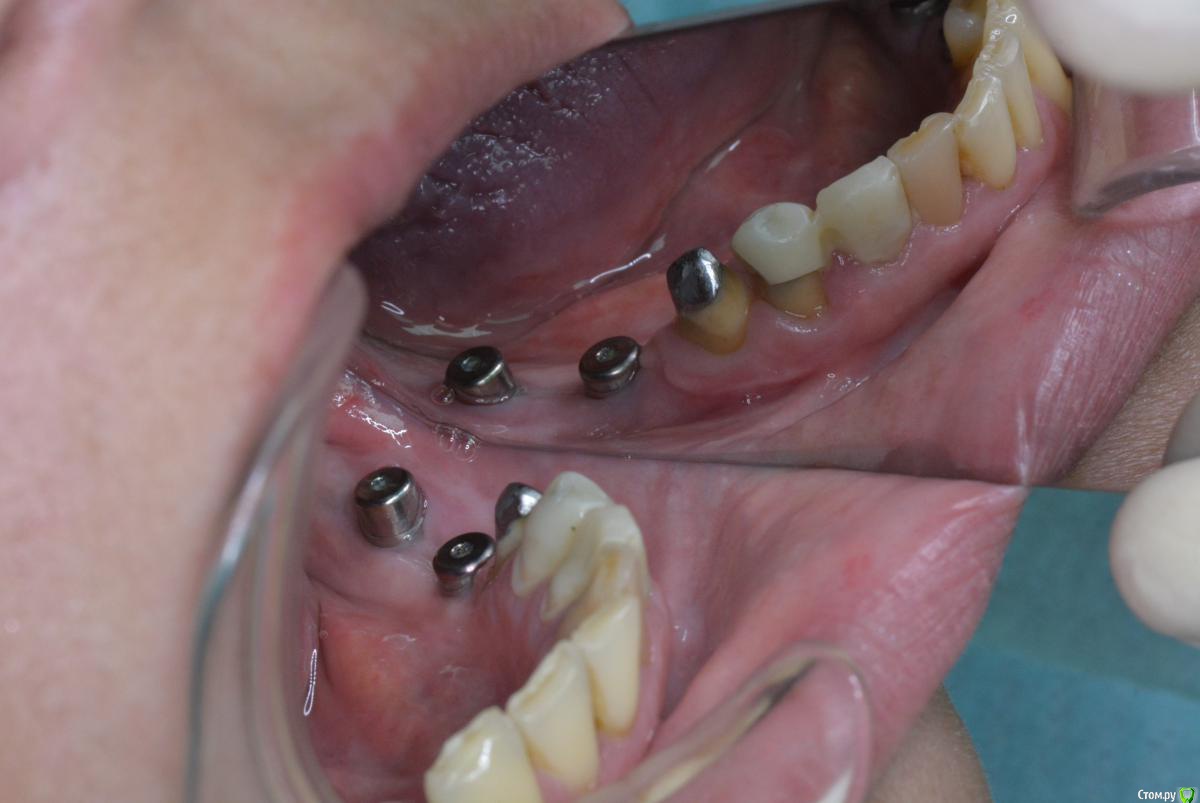

doktorenok Опубликовано 21 апреля, 2015 Поделиться Опубликовано 21 апреля, 2015 Ситуация следующая: в декабре 2013г проведена имплантация в 3 сегменте одномоментно с вертикальной аугментацией с применением мембраны Цитопласт (изначально над каналом было 4-5 мм). В июне 2014г раскрытие имплантов без манипуляций с мягкими тканями, ортопед вернул работу хирургу с просьбой сделать ткани прикрепленными. В июле 2014 г проведена пластика мягких тканей с применением Мукографта, направлен к ортопеду. Ортопед вернул хирургу с жалобами, что все подвижно. В ноябре 2014 г проведена операция углубления предверия по Казаньяну. На сегодняшний день ортопед опять недоволен, привел пациента ко мне и просит поправить ситуацию. Ситуация следующая: кератинизированной нет вообще, вестибулярно ткани очень тонкие, но прикрепленные, посередине между имплантов при натяжении щеки -слизистый тяж почти до середины гребня, язычно - ни прикрепленной, ни кератинизированной . Как бы Вы поступили? Варианты, которые вижу я:1. Оставить как есть, Пациент измучен. Но думаю будет периимплантит в ближайшем будущем.2. Вестибулярно- пересадка СДТ, язычно- деэпителизированный СДТ под расщепленный лоскут..3. Вестибулярно ничего не трогать, а язычно-деэпителизированный СДТ под расщепленный лоскут.4. Взять пошире СДТ , деэпителизировать его , надеть на формирователи и под расщепленный лоскут и язычно и вестибулярно.5. Заглушить импланты, пересадить СДТ. После приживления часть отдать на язычную сторону, а вестибулярную часть сместить апикально, или еще подсадить. Сама склоняюсь к 3 варианту.Проблема в том, что расщепить ткани вестибулярно будет сложно, они очень тонкие , будут рваться и разлезаться, и вестибулярно все очень бледное и в рубцах, то есть с кровоснабжением там плохо после нескольких хирургических вмешательств., боюсь получить некроз СДТ.Язычно - будет ли какой то результат от подсаженного деэпит. СДТ , учитывая тот факт, что кератинизированной нет вообще.На фотографиях все выглядит почему-то лучше, чем есть на самом деле. Фотограф я начинающий Поделитесь пожалуйста, кто как поступает в подобной ситуации? Ссылка на комментарий